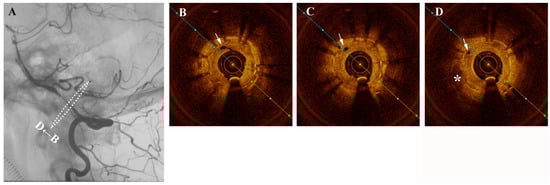

A middle-aged female presented one year after intracranial stenting for severe left intradural segment vertebrobasilar stenosis with recurrent vertigo. Digital subtraction angiography (DSA) confirmed severe in-stent restenosis and same-session optical coherence tomography (OCT) with an Ilumien Optis probe (St. Jude Medical, St. Paul, MN, USA) showed neovascularization-related neointimal hyperplasia (Figure 1). Figure 1 (A) Angiography confirming severe intracranial in-stent restenosis of the left intradural vertebral artery segment. Figure 1 (B–D) Pre-intervention cross-sectional optical coherence tomography (OCT) shows hypertrophic intima and hyporeflective microchannels (white arrow) originating directly from the lumen and penetrating contiguously towards the plaque (*). These are seen as hyporeflectile microchannels originating directly from the lumen, which penetrate contiguously towards irregular plaque and hyperplastic intimomedial complex. Neovascularization plays a role in intracranial atherosclerosis by providing trophic factors to plaque []. Such neovasculature is susceptible to intra-plaque hemorrhage and also importantly is a critical factor in the propagation of intimal hyperplasia following stenting []. Intracranial neovasculature cannot be resolved in-vivo by traditional imaging methods. In 2011, Mathews et al. performed OCT in the cavernous and the petrous segments of internal carotid artery, which used time-domain OCT assembled in a laboratory rather than a commercial product []. Although a small number of cases were enrolled, the result suggested that OCT examination of intracranial arteries was feasible. Until now, there have been numerous preliminary attempts at intracranial OCT use, but visualization of intracranial neovasculature has heretofore not been reported in a living patient. With the approximately 40 micron resolution afforded by OCT, an extremely rare and vivid look at the mechanisms behind plaque nutrition and neointimal hyperplasia of the intracranial vertebral artery is possible []. The in-stent stenosis was treated a Sequent Neo paclitaxel-coated balloon (B.Braun, Melsungen, Germany) for intimal hyperplasia inhibition (Figure 2). As plaque and neointimal morphologic characteristics are increasingly recognized as important contributors to disease prognosis and natural history, OCT may stand to inform treatment decisions and assess intimal tearing in the future.